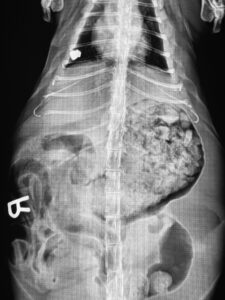

Taylor is the only cat in Tabby’s Place history (nearly 5,000 cats, which is 30 metric tons of cat) whose gut has been so glorious, it alarmed the vet team.

An emergency X-ray confirmed the diagnosis: “excess fat.”

If Tabby’s Place is here for another ten thousand years (as we fully intend), Taylor Ham’s X-ray will be forever celebrated.